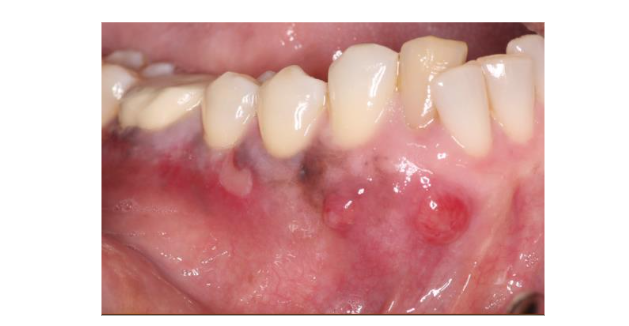

Figure 1. Preoperative clinical photo showing soft tissue lesions in the mucosa associated with tooth #26 and 27.